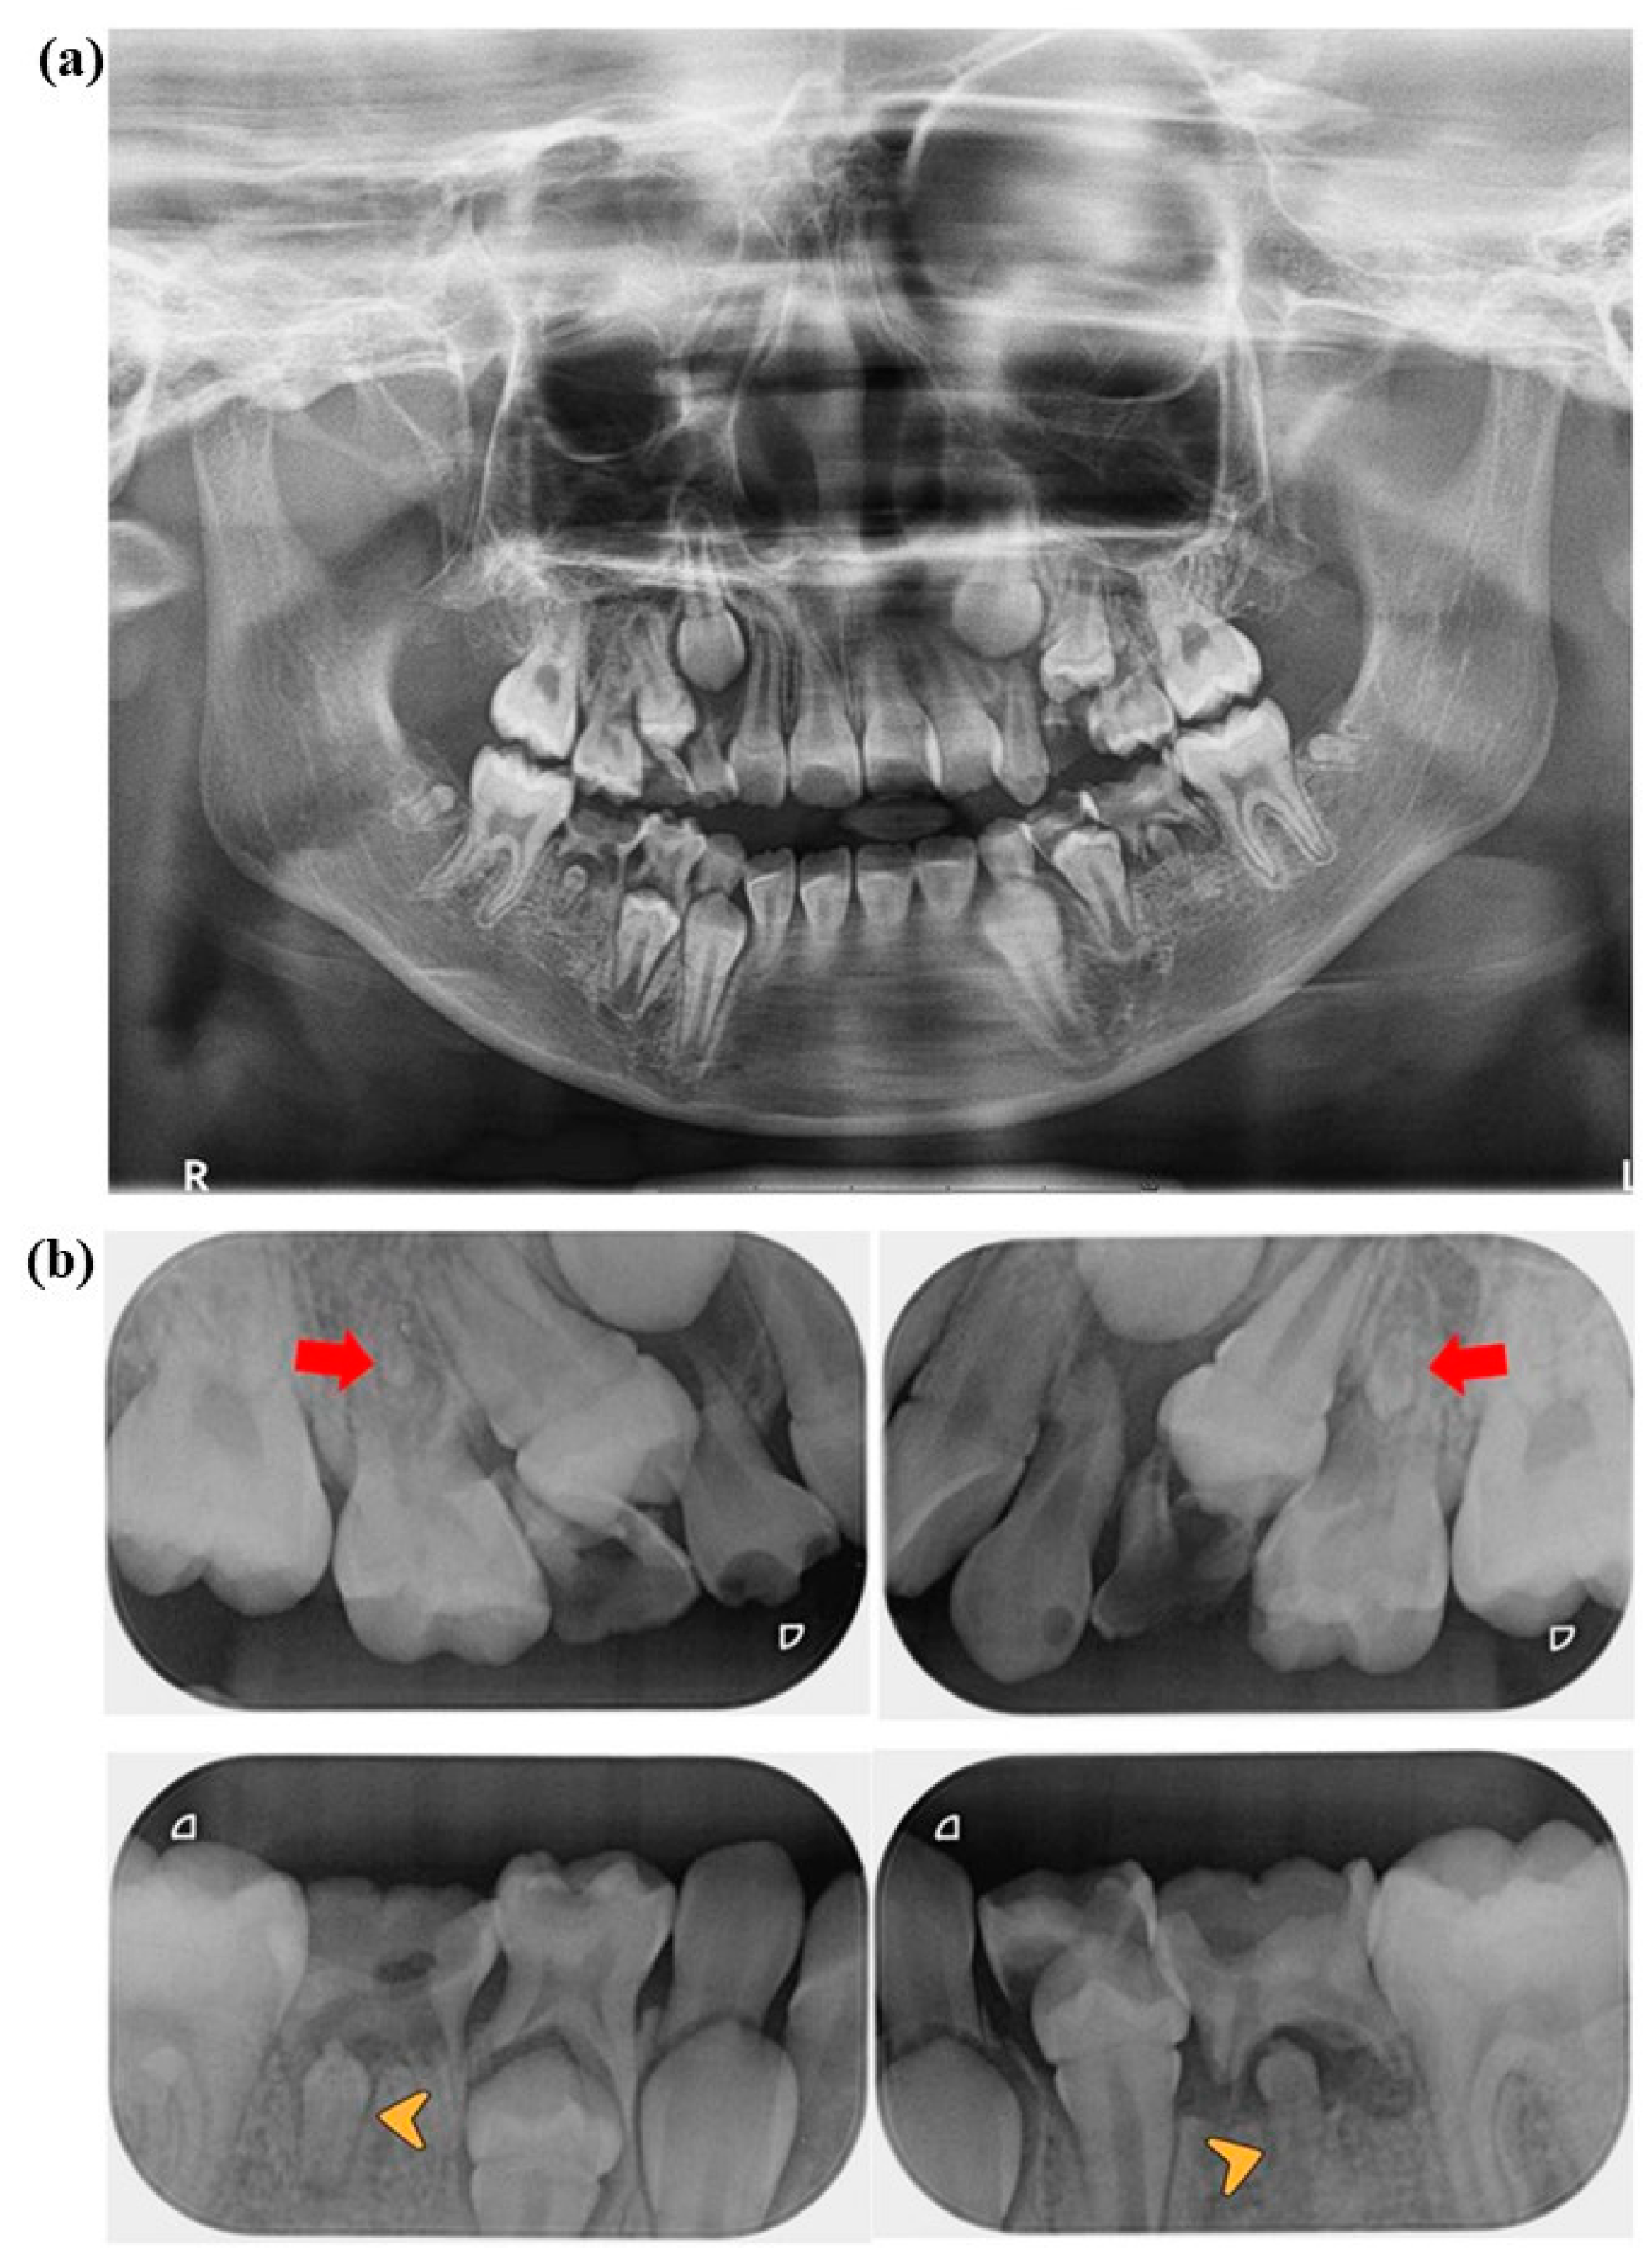

2. Case Presentation